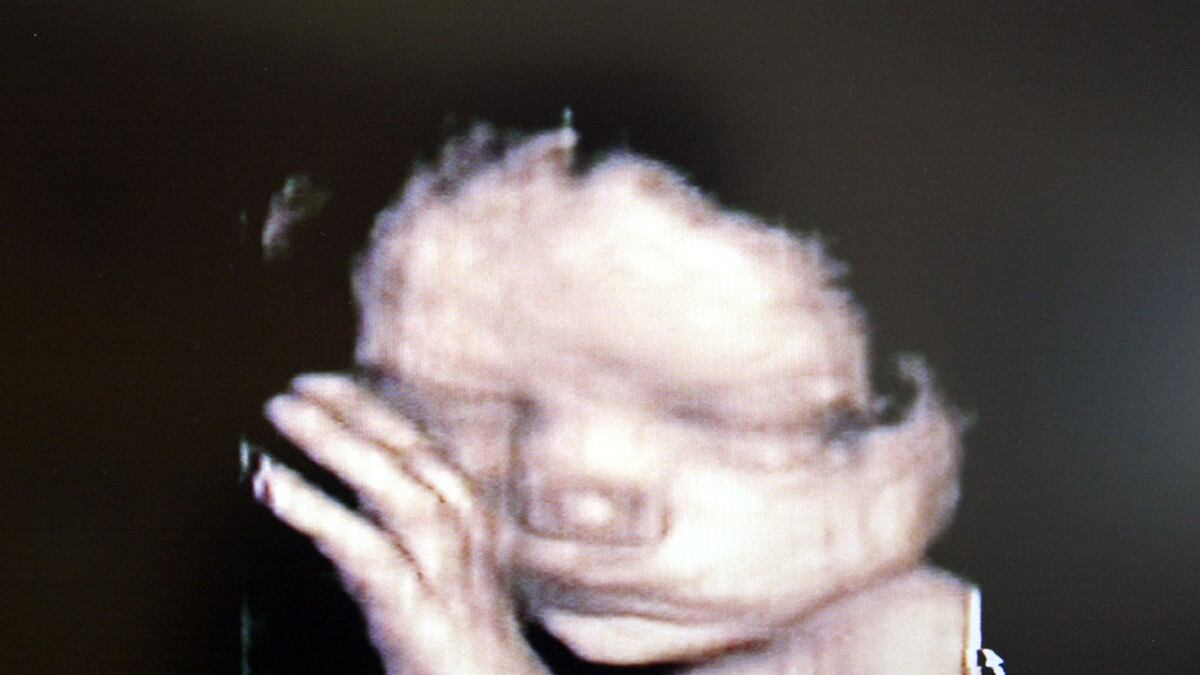

Substantial progress on this front was announced this week in the medical journal Science Translational Medicine, and reported widely, including in The New York Times. The researchers were able to cobble together almost the entire genetic sequence of a fetus without a direct sample from the fetus itself. They also showed that they could identify most of the “point mutations”—those genetically abnormal spots, aka genetic defects, along the spiraling double helix—that might lead to clinical abnormalities.

The novelty of the work is that it gathers critical information from a blood test from Mom (which contains good amounts of cell-free DNA from the fetus) and a saliva test from Dad—but nothing directly from Junior. The information gathered previously has required invasive methods, such as chorionic villous sampling, or CVS, which involves a biopsy of the placenta. This procedure, though generally safe, comes with a small risk of complication, including loss of the fetus. The better-known approach, amniocentesis, must be performed later in the pregnancy, meaning that, should an abnormality be found, decisions about termination must be made in a more compressed time frame. In addition, it too can be complicated by fetal loss and other problems.

Each of these scientific advances represents a remarkable achievement for the generation that spawned it—amnio in the 1950s, CVS in the 1980s, and the current genetic high-wire act just this week. And each has and promises to allow parents to make rational, if sometimes extremely painful, decisions about their family. Yet they also have created an enormous—really enormous problem: the excitement of inventing the tool, trying it out, and solving the puzzle has generated such scientific momentum that each has barreled headlong into a morass of impossibly complex ethical and spiritual issues without sufficient pause. As such, scientific information once again has gotten way out front of the clinically practical. What does it mean, really, if your 14-week-old fetus has a deletion on chromosome 12? No one has a clue, probably, but you’ll still be scared senseless (though the fear may recede by the child’s 30th or 40th birthday, I promise).